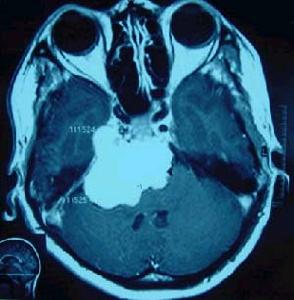

4.MRI檢查MRI對顯示鞍上小的生殖細胞瘤(直徑<1cm)或脊髓轉移灶十分清楚;顯示松果體區生殖細胞瘤常為圓形、橢圓形或不規則形多數T1為等或稍低信號,T2為稍高信號,少數亦可為等信號;注藥後均勻一致的強化,邊界清楚有時少數僅呈中度或不均勻強化有報告20%-58%的生殖細胞瘤有小的囊變,這些囊變由於蛋白性液體或壞死液化所致,通常極小,有時在瘤內有小出血灶,在T1像為高信號;松果體區者可侵犯中腦和丘腦在T2像上有周邊模糊高信號影。MRI對腫瘤的種植或播散顯示全面除了T1及T2像的多發病灶顯示清晰而注藥後病變明顯強化。底節生殖細胞瘤也是T1等或低信號而T2稍高信號,注藥後可均勻強化有的顯示同側皮層有萎縮現象。